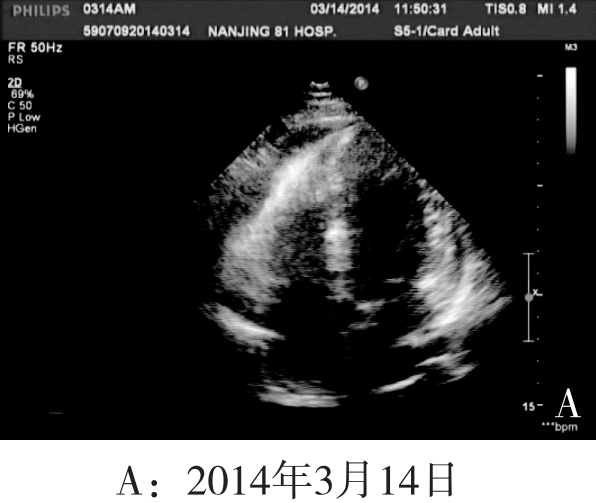

2014年4月28日:胸闷症状加重至3级,查体发现心音明显减弱、双下肢水肿1度。床边B超检查如图B所示心包大量积液,心尖部3.8cm(光标划中本行显示超声结果)。立即停止静脉输液、加强利尿,建议患者行心包穿刺抽液,被患者家属坚决拒绝并要求出院,随访得知当天死亡。